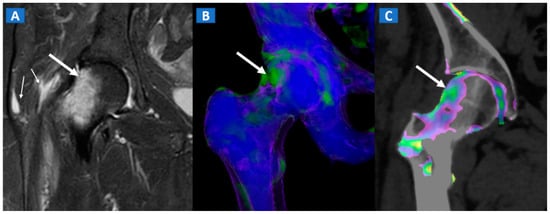

Figure 6.

A 46-year-old female with non-traumatic right hip pain. On the coronal STIR MRI image (A), hyperintense BME of the femoral neck is depicted (thick arrow), sparing the subchondral femoral head area. Note the associated trochanteric bursitis (thin arrows). The pattern of distribution of BME (arrow) is confirmed on the corresponding DECT coronal 3D image (B), and on the 1 mm coronal DECT image (C) (arrow).

Transient bone marrow oedema syndrome is a self-limiting disease characterized by pain and localized BME, which often affects lower limb joints. Besides confirming the tendency of BME to spare subchondral areas (Figure 6), DECT imaging can also rule out any associated findings to narrow the differential diagnosis. DECT is indeed capable to diagnose stress fractures, early AVN stages, and inflammatory arthropathies.